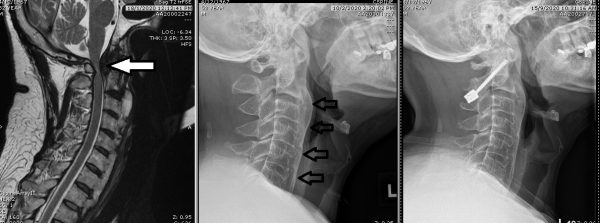

中图:第二至第七节颈椎有许多不正常的骨质增生,椎节之间互相吻合;

右图:后板颈椎减压及金属吻合手术。

彭老板苦着脸告诉我,他们彭家有不少亲人饱受骨刺所苦,而他的情况是颈椎韧带肥大和钙化,第二至第七节颈椎有许多不正常的骨质增生,椎节之间互相吻合,只剩下第一节和第二节颈椎可以转动,颈项僵硬,脖子转动的幅度也大大受限。

在医学上,彭老板的病症称为弥漫性特发性骨质增生(Diffuse idiopathic skeletal hyperostosis, DISH),俗称“骨刺”或“骨赘”。由于肥大及钙化的韧带压迫神经中枢,造成他四肢乏力,且经常有酥麻刺痛的感觉,手脚不灵活,走路时,每一步都像踩在云端上,令他极度缺乏安全感。

我在电脑导航的协助下,替彭老板进行后板颈椎减压及金属吻合手术,将颈椎第一和第二节的后板切除,以螺丝加以固定。如此一来,颈颈的活动范围虽然受到限制,但神经中枢不再受压,四肢无力、麻木和刺痛的问题也迎刁而解。